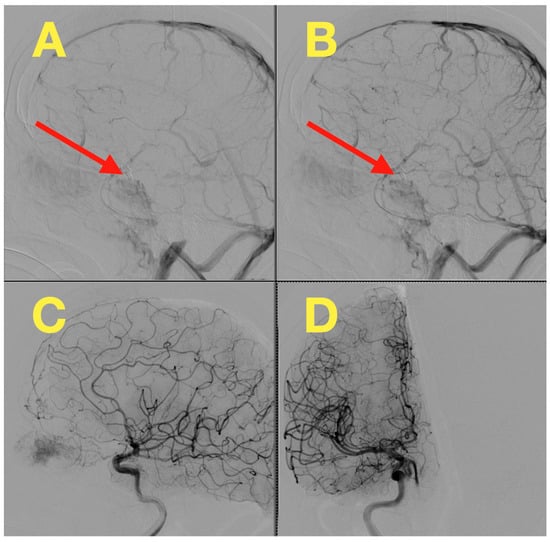

2. Case Presentation